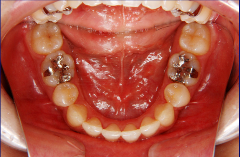

口腔内写真,レントゲン

装置装着後

口腔内写真、レントゲン(必要に応じて CT )、印象(歯型)採得